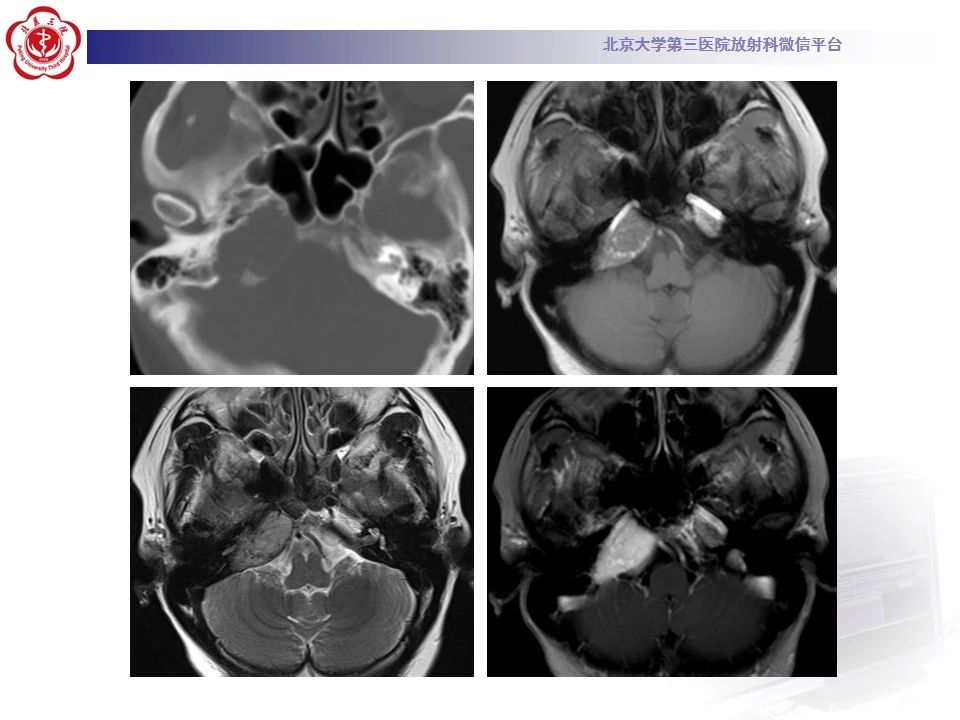

作者:北京大学第三医院 徐慧敏 邬海博

来源:北京大学第三医院放射科